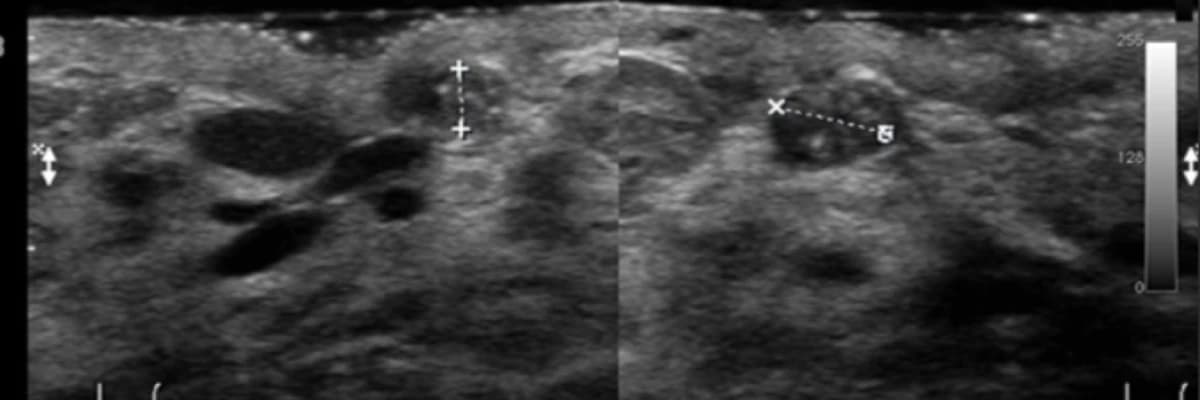

Elbette tarama amaçlı muayenelerimizde daha önceden bildiğimiz kitlelerin durumunu da inceleriz. Bir kitlenin “iyi huylu” olduğundan emin olsak bile “şüpheli” herhangi bir yeni bulgu taşıyıp taşımadığına bakmak zorundayız: kitlenin şeklinde, kenarlarının düzeninde, iç yapısında, damarlanma özelliklerinde ve boyutlarında eskiye göre anlamlı bir farklılık var mı? Bu süreci tek bir radyologla götürmeyi tercih etmeli ve radyoloğunuzu özenle seçmelisiniz çünkü radyologların aynı vakadaki yorumları birbirinden farklı olabilir.

Radyoloğun yorum ve önerileri kaderinizi etkiler! Bir fibroadenomda yeni bulgular ortaya çıkması son derece istisnai bir durumdur ama varsa önemli olabilir ve biyopsiyi gerektirebilir. Yine de bu biyopsilerin çoğunda kanser çıkmaz. Fibroadenomların 10.000’de 2′ sinde kanser başlayabilir ama bu ihtimal, memenizin herhangi bir yerinde kanser başlaması ihtimalinden daha yüksek değildir. Üstelik bu kanserin, memenizin başka bir yerindeki yeni bir kanserden fazlası yoktur, genellikle azı vardır. Fibroadenomların içinde başlayan kanseröz değişikliklerin %90’ı in situ lobuler yada in situ duktal tiptedir ve gerçek anlamda kanser bile değildir; sadece kanser gelişimi için “yüksek risk” anlamı taşır. Bu değişiklikler memeden herhangi bir nedenle alınan parçalarda çok sık rastlanan ama sadece mikroskopla görülebilen (elle yada gözle seçilemeyen) “tesadüfi” patolojik bulgulardır. Kanser dışı nedenlerden ölen ve otopsi yapılan kadınların memelerinde bunlara çok sık rastlanır; kısacası önemsizdir! Meme kanseri taramalarınız düzenli ve kaliteliyse ve belli bir meme radyoloğunun takibindeyseniz bu kanserin de en erken evrede (Evre 0 yada1) yakalanması çok kolaydır. Türkiye’de taramalara rağmen meme kanserleri genellikle bu kadar erken evrelerde bulunamamakta, diğer yandan her yıl yüzbinlerce kadın gerçek dışı gerekçelerle gereksiz yere ameliyat edilmektedir.